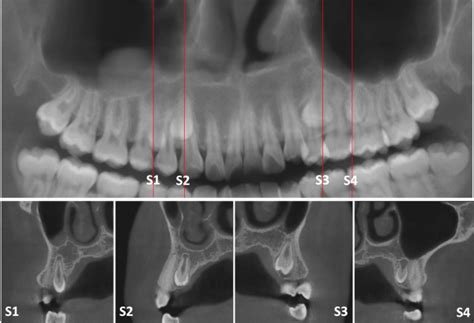

Radiografía panorámica mostrando dientes supernumerarios en el arco superior.

Un diente supernumerario es una pieza dentaria adicional a la formula normal (20 dientes en la dentición temporal y 32 en la permanentes). Puede presentarse en las diferentes etapas del desarrollo humano, tanto en la dentición temporal como en la mixta y permanente; constituyen uno de los factores que se asocian a la etiología de las maloclusiones y ocasionan alteraciones en la línea media, retención de piezas dentarias, apiñamientos, resorción radicular, diastemas y malformación de otros dientes. Se encuentran en cualquier región de la arco y sólo se pueden visualizar radiográficamente.

Los sitios más frecuentes donde se ubican los dientes SN son: maxilar superior, línea media, región palatina superior de incisivos superiores, región premolar inferior, y región distal al tercer molar, tanto el maxilar como en la mandíbula. En los casos de SN múltiples existe una predilección por la región premolar inferior, seguida de la región molar y de la región anterior.

El diagnóstico temprano de los dientes supernumerarios es importante para evitar que se presenten complicaciones. Éste puede realizarse a través de la exploración clínica y radiográfica y su tratamiento dependerá de la posición y clase de supernumerario, así como el efecto sobre el diente temporal o permanente.